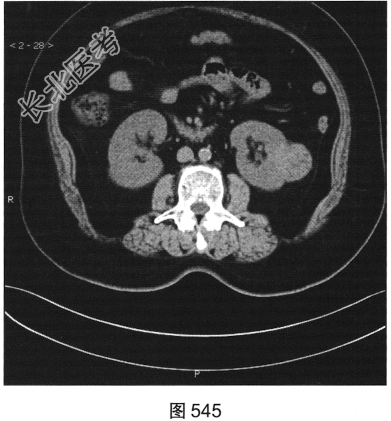

- 多项选择题3.[提示]CT平扫+增强(图545~图549):左肾下极背外侧软组织密度灶, 部分突出于肾实质外,其内可见低密度坏死灶, 增强扫描强化不均匀,平扫、皮质、实质、排泌CT值36HU、92HU、73HU、53HU。可考虑的鉴别诊断为( )

A、肾嗜酸性粒细胞腺瘤

B、出血性囊肿

C、肾血管平滑肌脂肪瘤

D、肾细胞癌

E、肾转移瘤

F、淋巴瘤